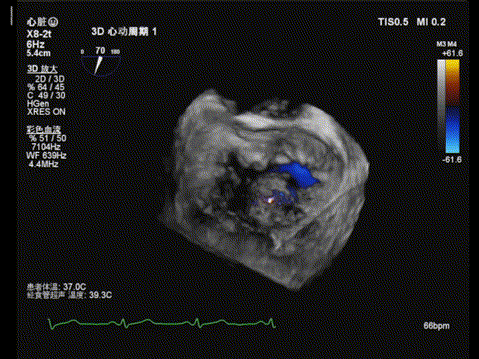

术前TEE显示二尖瓣重度反流,反流主要来源于2区